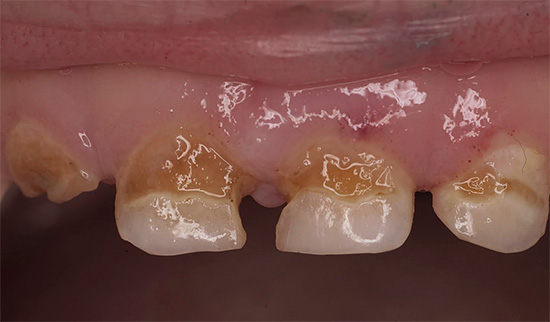

La carie cronica può essere osservata anche nei denti primari. Questa è una delle malattie più comuni nei bambini, poiché può essere difficile per i genitori tenere traccia delle condizioni dei loro denti in tenera età. A volte il dentista deve affrontare i problemi del decorso acuto della carie, quando in pochi mesi la carie del bambino nella fase spot si trasforma in profonde violazioni del tessuto dentale. In questo caso, è necessario interrompere immediatamente il suo sviluppo conducendo un trattamento complesso di tutti i fuochi.

Un aspetto tipico dei denti con carie cronica è mostrato nella foto qui sotto:

Non ci sono lesioni estese dei denti e in alcuni punti le aree scure sono di dimensioni molto ridotte e spesso non attirano l'attenzione del paziente. Di solito il dolore è assente.

Il decadimento cronico dei denti decidui si sviluppa per gli stessi motivi (un esempio è la cosiddetta carie di bottiglia). Spesso, la procrastinazione dei genitori nell'abituare il bambino all'igiene orale porta alla comparsa di focolai della malattia, che potrebbero essere evitati se si osservassero le regole elementari: regolare spazzolatura e risciacquo della bocca dopo aver mangiato.

Inoltre, la carie cronica nei bambini spesso non viene percepita dai genitori come una malattia in generale. Le lesioni cariate separate sono attribuite al fascino dei bambini con i dolci e molti genitori non prestano attenzione alla prevenzione e al trattamento, perché credono che se i denti del bambino cadono ancora, non vale la pena torturare il bambino dal dentista e spendere soldi per le cure. Di conseguenza, le misure necessarie non vengono prese in tempo e, di conseguenza, le singole lesioni diventano croniche.